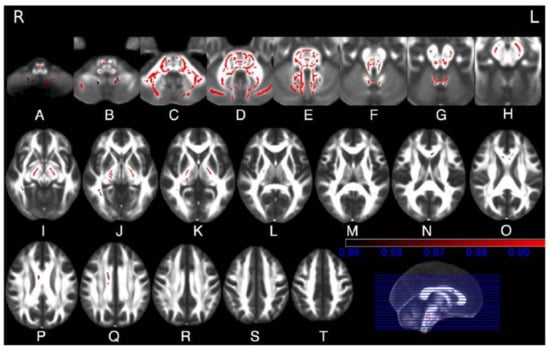

- Scherfler, C.; Boesch, S.M.; Donnemiller, E.; Seppi, K.; Weirich-Schwaiger, H.; Goebel, G.; Virgolini, I.; Wenning, G.K.; Poewe, W. Topography of cerebral monoamine transporter availability in families with SCA2 mutations: A voxel-wise [123I]beta-CIT SPECT analysis. Eur. J. Nucl. Med. Mol. Imaging 2006, 33, 1084–1090. [Google Scholar] [CrossRef] [PubMed]

- Adanyeguh, I.M.; Perlbarg, V.; Henry, P.G.; Rinaldi, D.; Petit, E.; Valabregue, R.; Brice, A.; Durr, A.; Mochel, F. Autosomal dominant cerebellar ataxias: Imaging biomarkers with high effect sizes. NeuroImage Clin. 2018, 19, 858–867. [Google Scholar] [CrossRef] [PubMed]